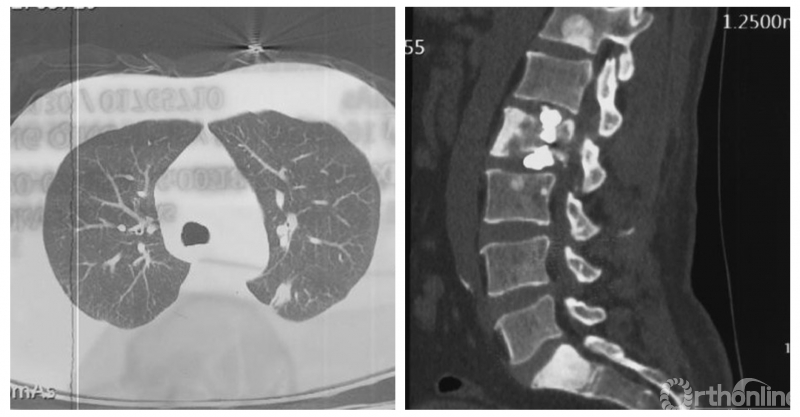

患者房某,男性、51岁。主因“腰痛3个月”入院,既往外院诊断“周围型肺腺癌”,全身检查提示多发骨转移。

经Spine Oncology Study Group(SOSG)评估硬膜外脊髓压迫(ESCC)为Grade 1a型,轻度脊髓压迫;脊柱机械稳定性评估(SINS)7分,中度不稳。修正Tokuhashi评分(RTS)6分,预计生存<6个月,建议姑息性手术及保守治疗;结合Tomita评分系统6分,故行姑息性手术短期控制。

影像学资料

入院影像学资料